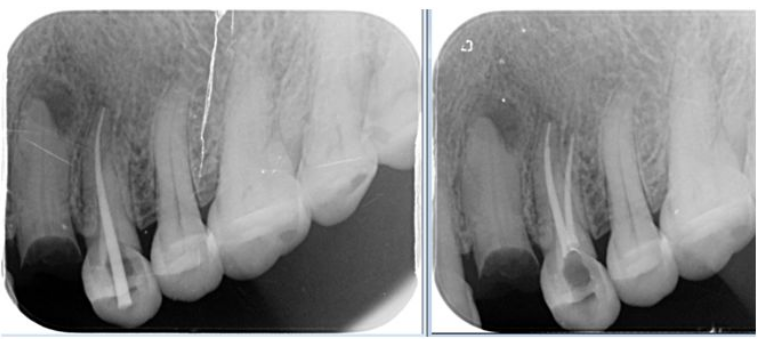

治疗失败引起一系列后遗症,担心根管治疗的"杀神经"操作对牙齿伤害大

德州市中医院口腔科|"根管治疗"就是"抽牙神经"吗?